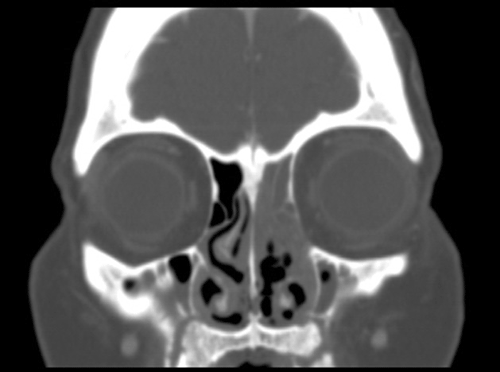

Image of the Case: CT scan, coronal view, of the sinuses reveals an opacified left ostiomeatal unit on the left and thickening of the mucosa on the right (Panel A). CT scan, axial view. The hard palate and maxilla show destructive changes and fractures causing a “moth-eaten” appearance (Panel B).

Clinical information: The patient was a 42 year-old woman with a history of acute promyelocytic leukemia status post Atra and induction chemotherapy with Idarubicin and ARA-C was admitted to the hospital for consolidation therapy. During her hospitalization she developed mucositis which gradually progressed for a few weeks. Her symptoms included sinus pain (left significantly greater than right), sinus drainage, mouth pain (particularly on the soft palate), and facial swelling. Computerized tomography (CT) scan revealed destructive changes of the hard palate and maxilla, and surgical intervention was required. Intra-operative findings included bilateral diffuse necrosis of the nasal cavities, with significant destruction of the nasal septum, left nasal turbinate, and bony nasal floor. Specimens were sent for frozen section, permanent section, and fungal cultures. The patient received antifungal therapy and required repeated sino-nasal debridement. There has been no further extension of fungal infection. Following are images from permanent section.